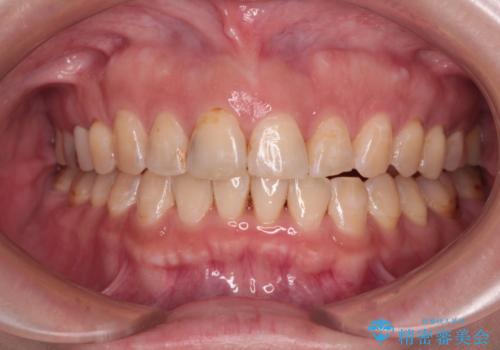

[ 前歯開咬 ] 前歯が噛んでいない マウスピース矯正治療

担当医 大元洋佑